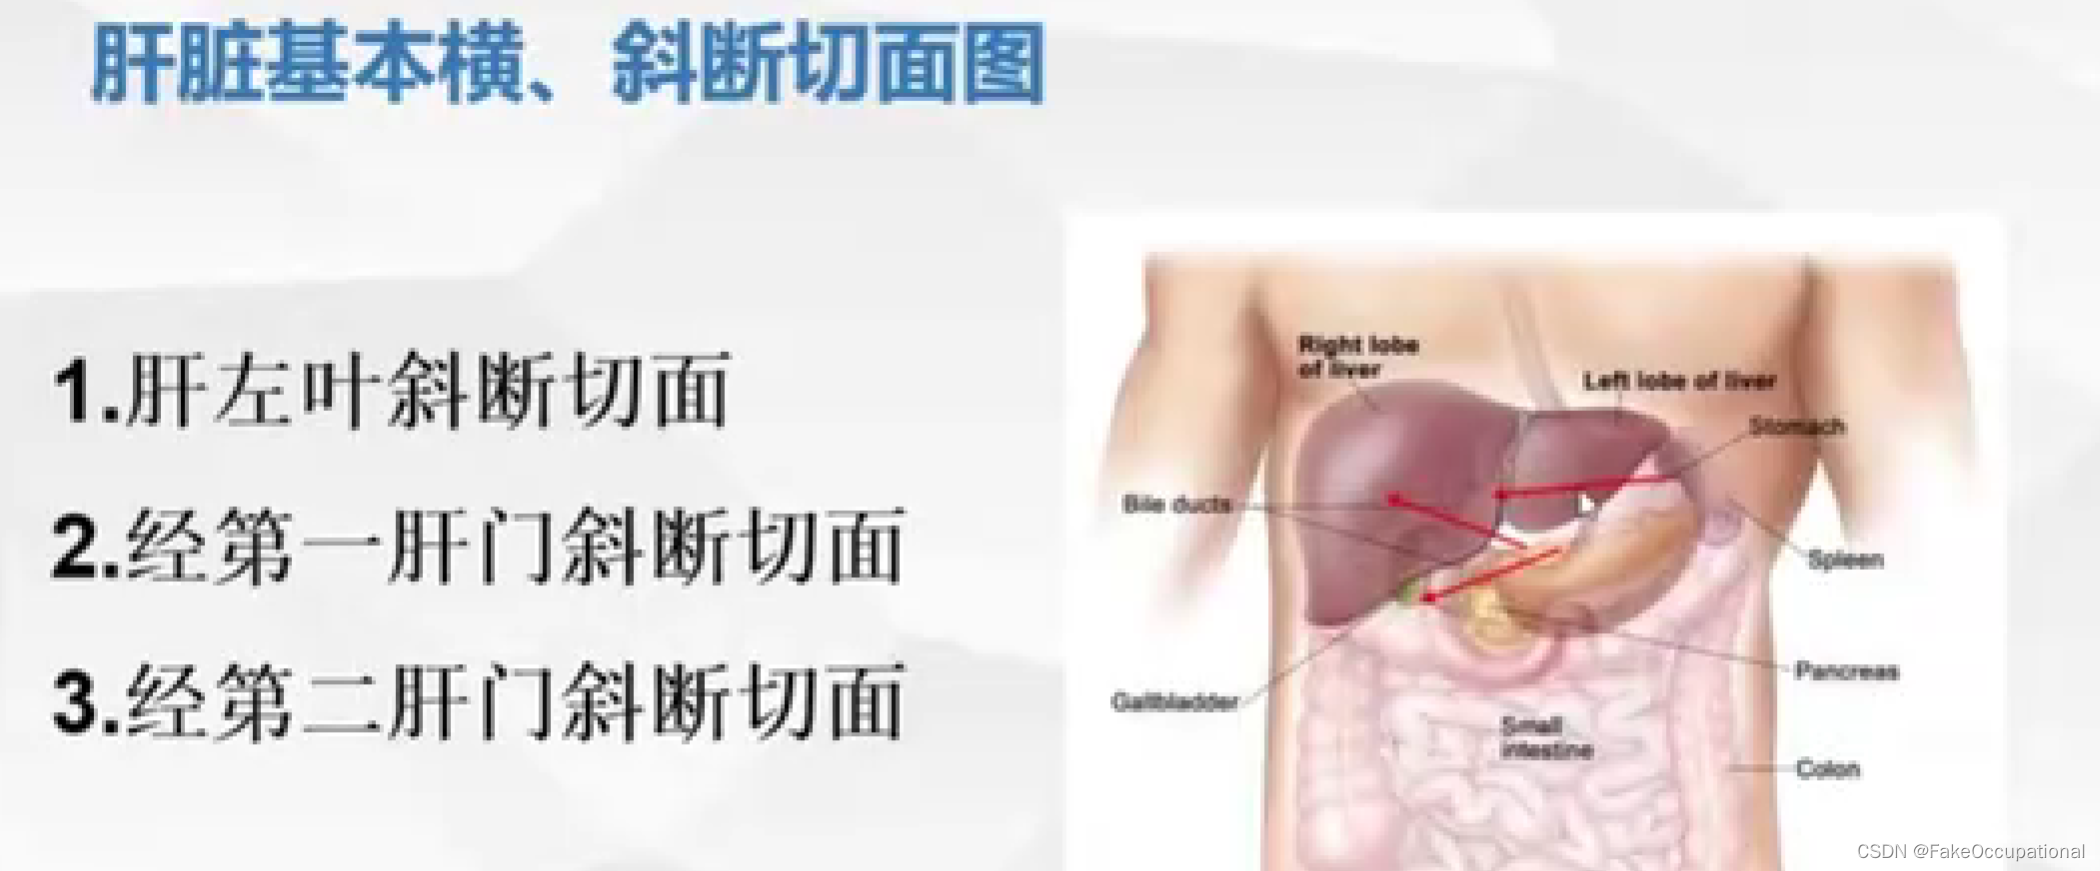

肝脏解剖概要

肝脏超声检查技术